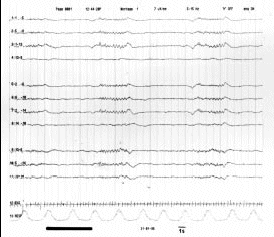

Figura 9.- Trazado electroencefalográfico de paciente en coma. Se observa un patrón salva-supresión: intervalos de actividad e intervalos de profunda depresión de la misma.